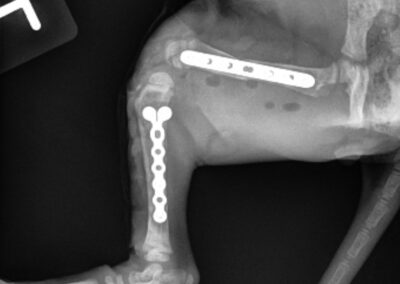

Tibial Plateau Leveling Osteotomy (TPLO)

TPLO is a surgical technique that stabilizes the knee by altering the biomechanics of the joint. By changing the angle of the tibial plateau, the procedure eliminates the need for the cranial cruciate ligament during weight bearing, helping to improve comfort and function during movement.

Tibial Plateau Leveling Osteotomy (TPLO) #1

Tibial Plateau Leveling Osteotomy (TPLO) #2

Tibial Plateau Leveling Osteotomy (TPLO) #3